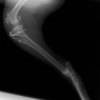

術前側面像

術後側面像

術前に25°であったTPAは、TPLO実施により7°に矯正されました。症例の歩行状態は良好です。